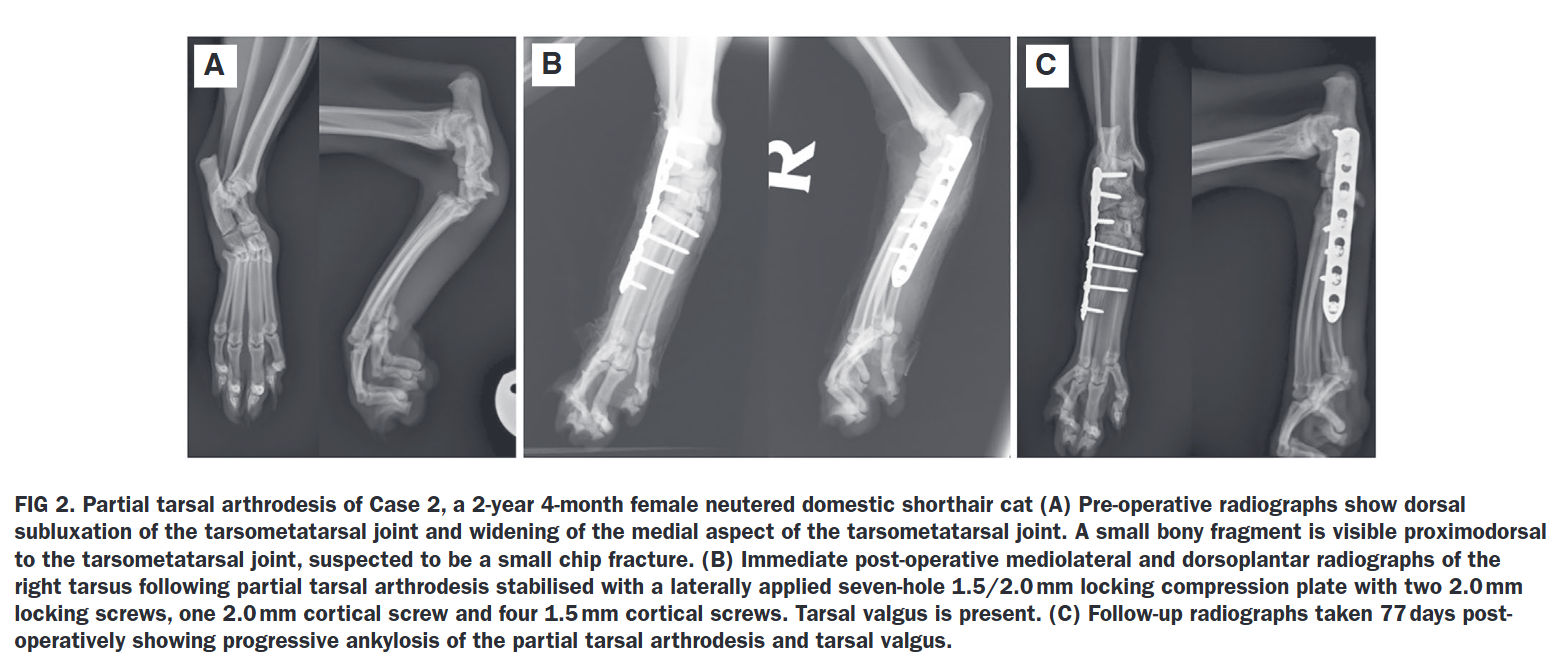

총 5마리의 고양이(보호자가 있는 환자)가 연구에 포함되었습니다. 모든 환자는 내측 또는 외측에 플레이트(bone plate)를 적용하여 부분 발목 관절 고정술을 받았습니다. 연구진은 환자의 성별, 수술 당시 나이, 파행 정도, 수술 기법, 합병증, 그리고 수술 후 60일에서 87일 사이의 임상 및 방사선학적 추적 관찰(Follow-up) 결과를 분석했습니다.

- 수술적 접근 및 고정: 3마리는 외측(lateral)으로, 2마리는 내측(medial)으로 플레이트를 적용하여 고정했습니다. 모든 환자에서 관절 연골을 제거(debridement)하고 탈회골기질(DBM)을 이식했습니다.

- 합병증: 수술 중 발생한 합병증은 없었습니다. 수술 후 합병증으로는 5마리 중 4마리에서 수술 부위 다리의 부종(swelling)이 관찰되었으나 치료 없이 모두 소실되었습니다. 1마리에서는 플레이트의 윤곽 성형(contouring) 미비로 인한 경미한 의인성 발목 외반(tarsal valgus)이 관찰되었습니다. 주요하거나 치명적인 합병증은 보고되지 않았습니다.